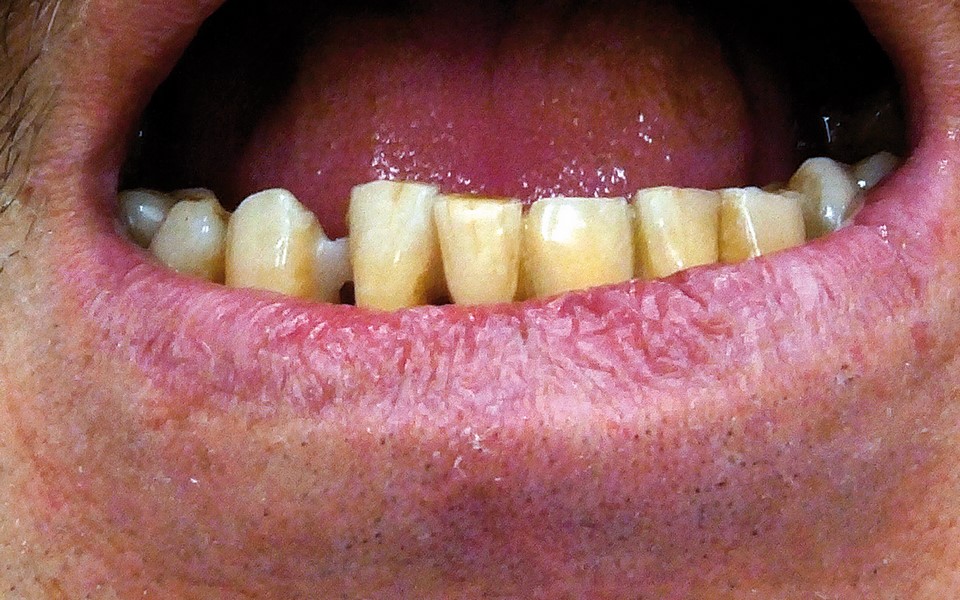

Jedną z popularniejszych metod stabilizacji zębów rozchwianych jest ich szynowanie. Metoda ta, wspierająca inne metody leczenia, jest powszechnie stosowana. Jednym z najnowocześniejszych materiałów wykorzystywanych w stomatologii do szynowania zębów jest taśma poliaramidowa. W opisanym przypadku autorzy pracy przedstawiają sposób uproszczenia całej procedury i ograniczenia ryzyka popełnienia błędu, szczególnie w sytuacji całkowitej utraty zęba. Uzyskano to dzięki zastosowaniu indeksu wykonanego z przezroczystego silikonu.

One of the more popular methods of stabilising loose teeth is to splint them. This method, aiding other methods of treatment, is generally used. One of the most modern materials used in dentistry for splinting teeth, is polyamide tape. In the case described the authors show how to simplify the whole procedure and limit the risk of making a mistake, particularly in the situation of total loss of one tooth. This was achieved thanks to the use of an index made out of transparent silicone.